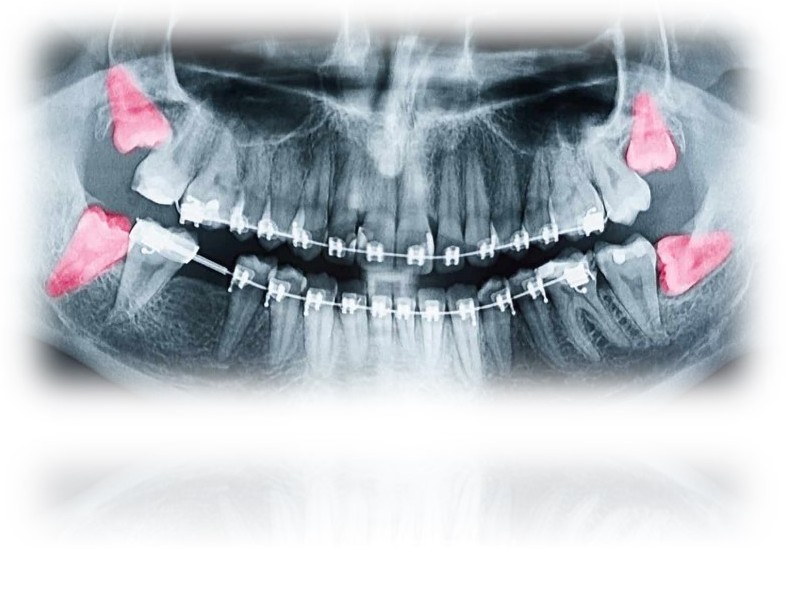

Wisdom teeth, or third molars, are the final set of molars located at the back of the mouth. Most people have four wisdom teeth—two in the upper jaw and two in the lower. These teeth typically emerge between ages 16 and 25.

While some wisdom teeth fully erupt, others may partially emerge or fail to develop. Impacted wisdom teeth, which lack sufficient space to emerge properly, are a frequent issue.

Complications from an Impacted Tooth

Teeth Misalignment: Pressure causing adjacent teeth to shift.

Protect Alignment: Prevent crowding or shifting of your teeth.